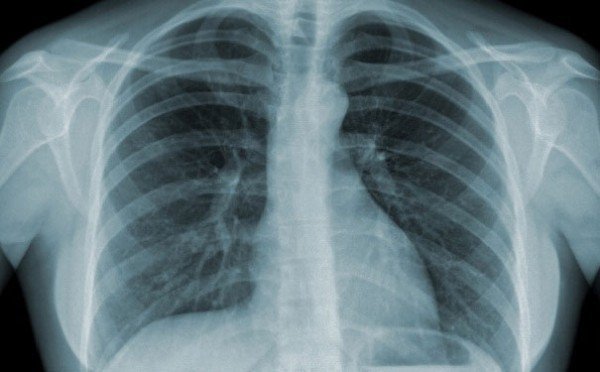

Chụp X quang là một thuật ngữ khá phổ biến và quen thuộc trong y học. Vậy X quang là gì và chụp X quang để làm gì? Dưới đây là 22 câu trả lời về các vấn đề liên quan đến bức xạ tia X, cũng như những lợi ích đi kèm rủi ro của chúng.